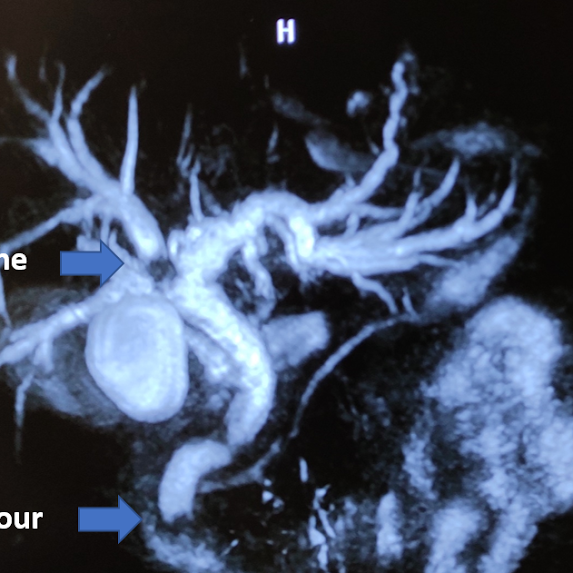

Cancer care continues in times of COVID pandemic. Interesting case with a tumour in distal bile duct and a stone in proximal biliary tree managed successfully with surgery (pylorus preserving pancreaticoduodenectomy with stone clearance). Pylorus preservation during surgery helps patients eat normally after after surgery with preserved gastric capacity compared to whipple operation with reduced metabolic side effects of surgery. With a dedicated team taking care of patients and hand holding them, the patients are able to start walking soon after surgery and recover faster.